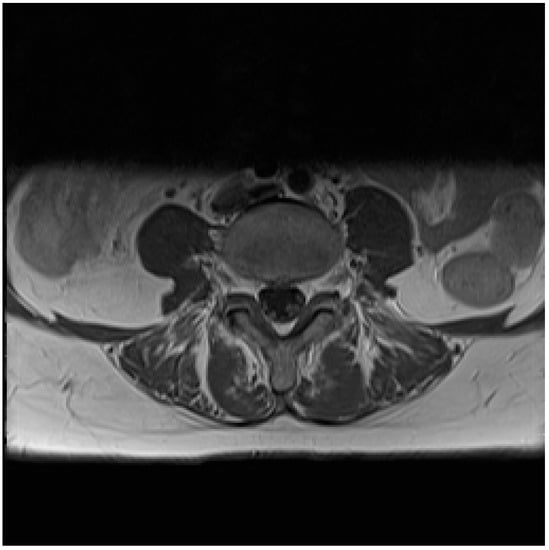

Lyme Neuroborreliosis in a Patient with Breast Cancer: MRI and PET/CT Findings

Abstract